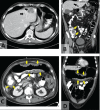

Entamoeba histolytica infections of the gastrointestinal tract are common in the developing world but rare in North America. The authors present two cases: one involving an individual who had not travelled to an endemic area and another involving an individual who was born in Bulgaria. Both presented with severe abdominal pain and diarrhea. Endoscopic assessment revealed scattered colonic ulcerations and one patient was found to have a liver abscess on imaging. Stool ova and parasite studies were negative in both cases and both were diagnosed on review of colonic biopsies. On review of all Entamoeba cases in the Calgary Health Zone (Alberta), ova and parasite analysis found an average of 63.7 Entamoeba cases per year and a pathology database review revealed a total of seven cases of invasive E histolytica (2001 to 2011). Both patients responded well to antibiotic therapy. E histolytica should be considered in new-onset colitis, especially in individuals from endemic areas.